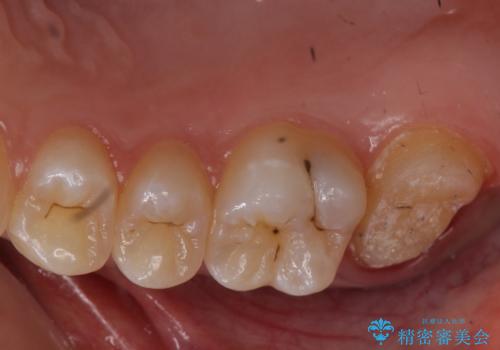

- 奥歯が虫歯になり、位置的に詰め物は難しかったため、被せものにする治療を行いました。

- 11万円 ジルコニアクラウンスタンダード10万円、仮歯1万円費用は治療当時の料金となります

頬側に咬頭が一つ多い歯であったのと、歯肉に近い位置が虫歯になっていたため、被せものでしっかり覆う治療を行いました。